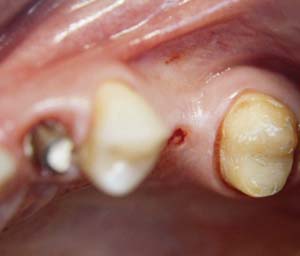

A 45-year-old female was referred for implant placement and prosthetic treatment in the area of tooth No. 24. The tooth had been extracted 4 years prior; the patient did not wear any denture thereafter. The radiograph revealed adequate bone height and a 5-mm to 6-mm ridge at the crest (Figure 2). It was decided to place a 11.5 mm in length, 3.75 mm in diameter Tapered Screw-Vent® implant (Zimmer Dental, www.zimmerdental.com) using the alveolar remodeling technique in the area of tooth No. 24.

At the time of surgery, local infiltrative anesthesia was administered (lidocaine 2% with epinephrine, 1:100,000). A full-thickness mucoperiosteal flap was raised. The initial osteotomy was performed on midcrestal bone using a rose-headed bur. To prepare the osteotomy site for implant placement, sequential alternating osteotomes with variable conicity were used, drilling 2-mm shorter than the length of the implant to be placed (Figure 3A and Figure 3B). The implants presented initial primary stability (Figure 4), the cover screws were placed, and the implants were submerged for a healing period. The tissue was approximated, and the patient was instructed not to wear any denture or to place pressure on the healing site.

Figure 2 Preoperative view of the area around tooth No. 24. On the left, a previously placed implant abutment

is visible.